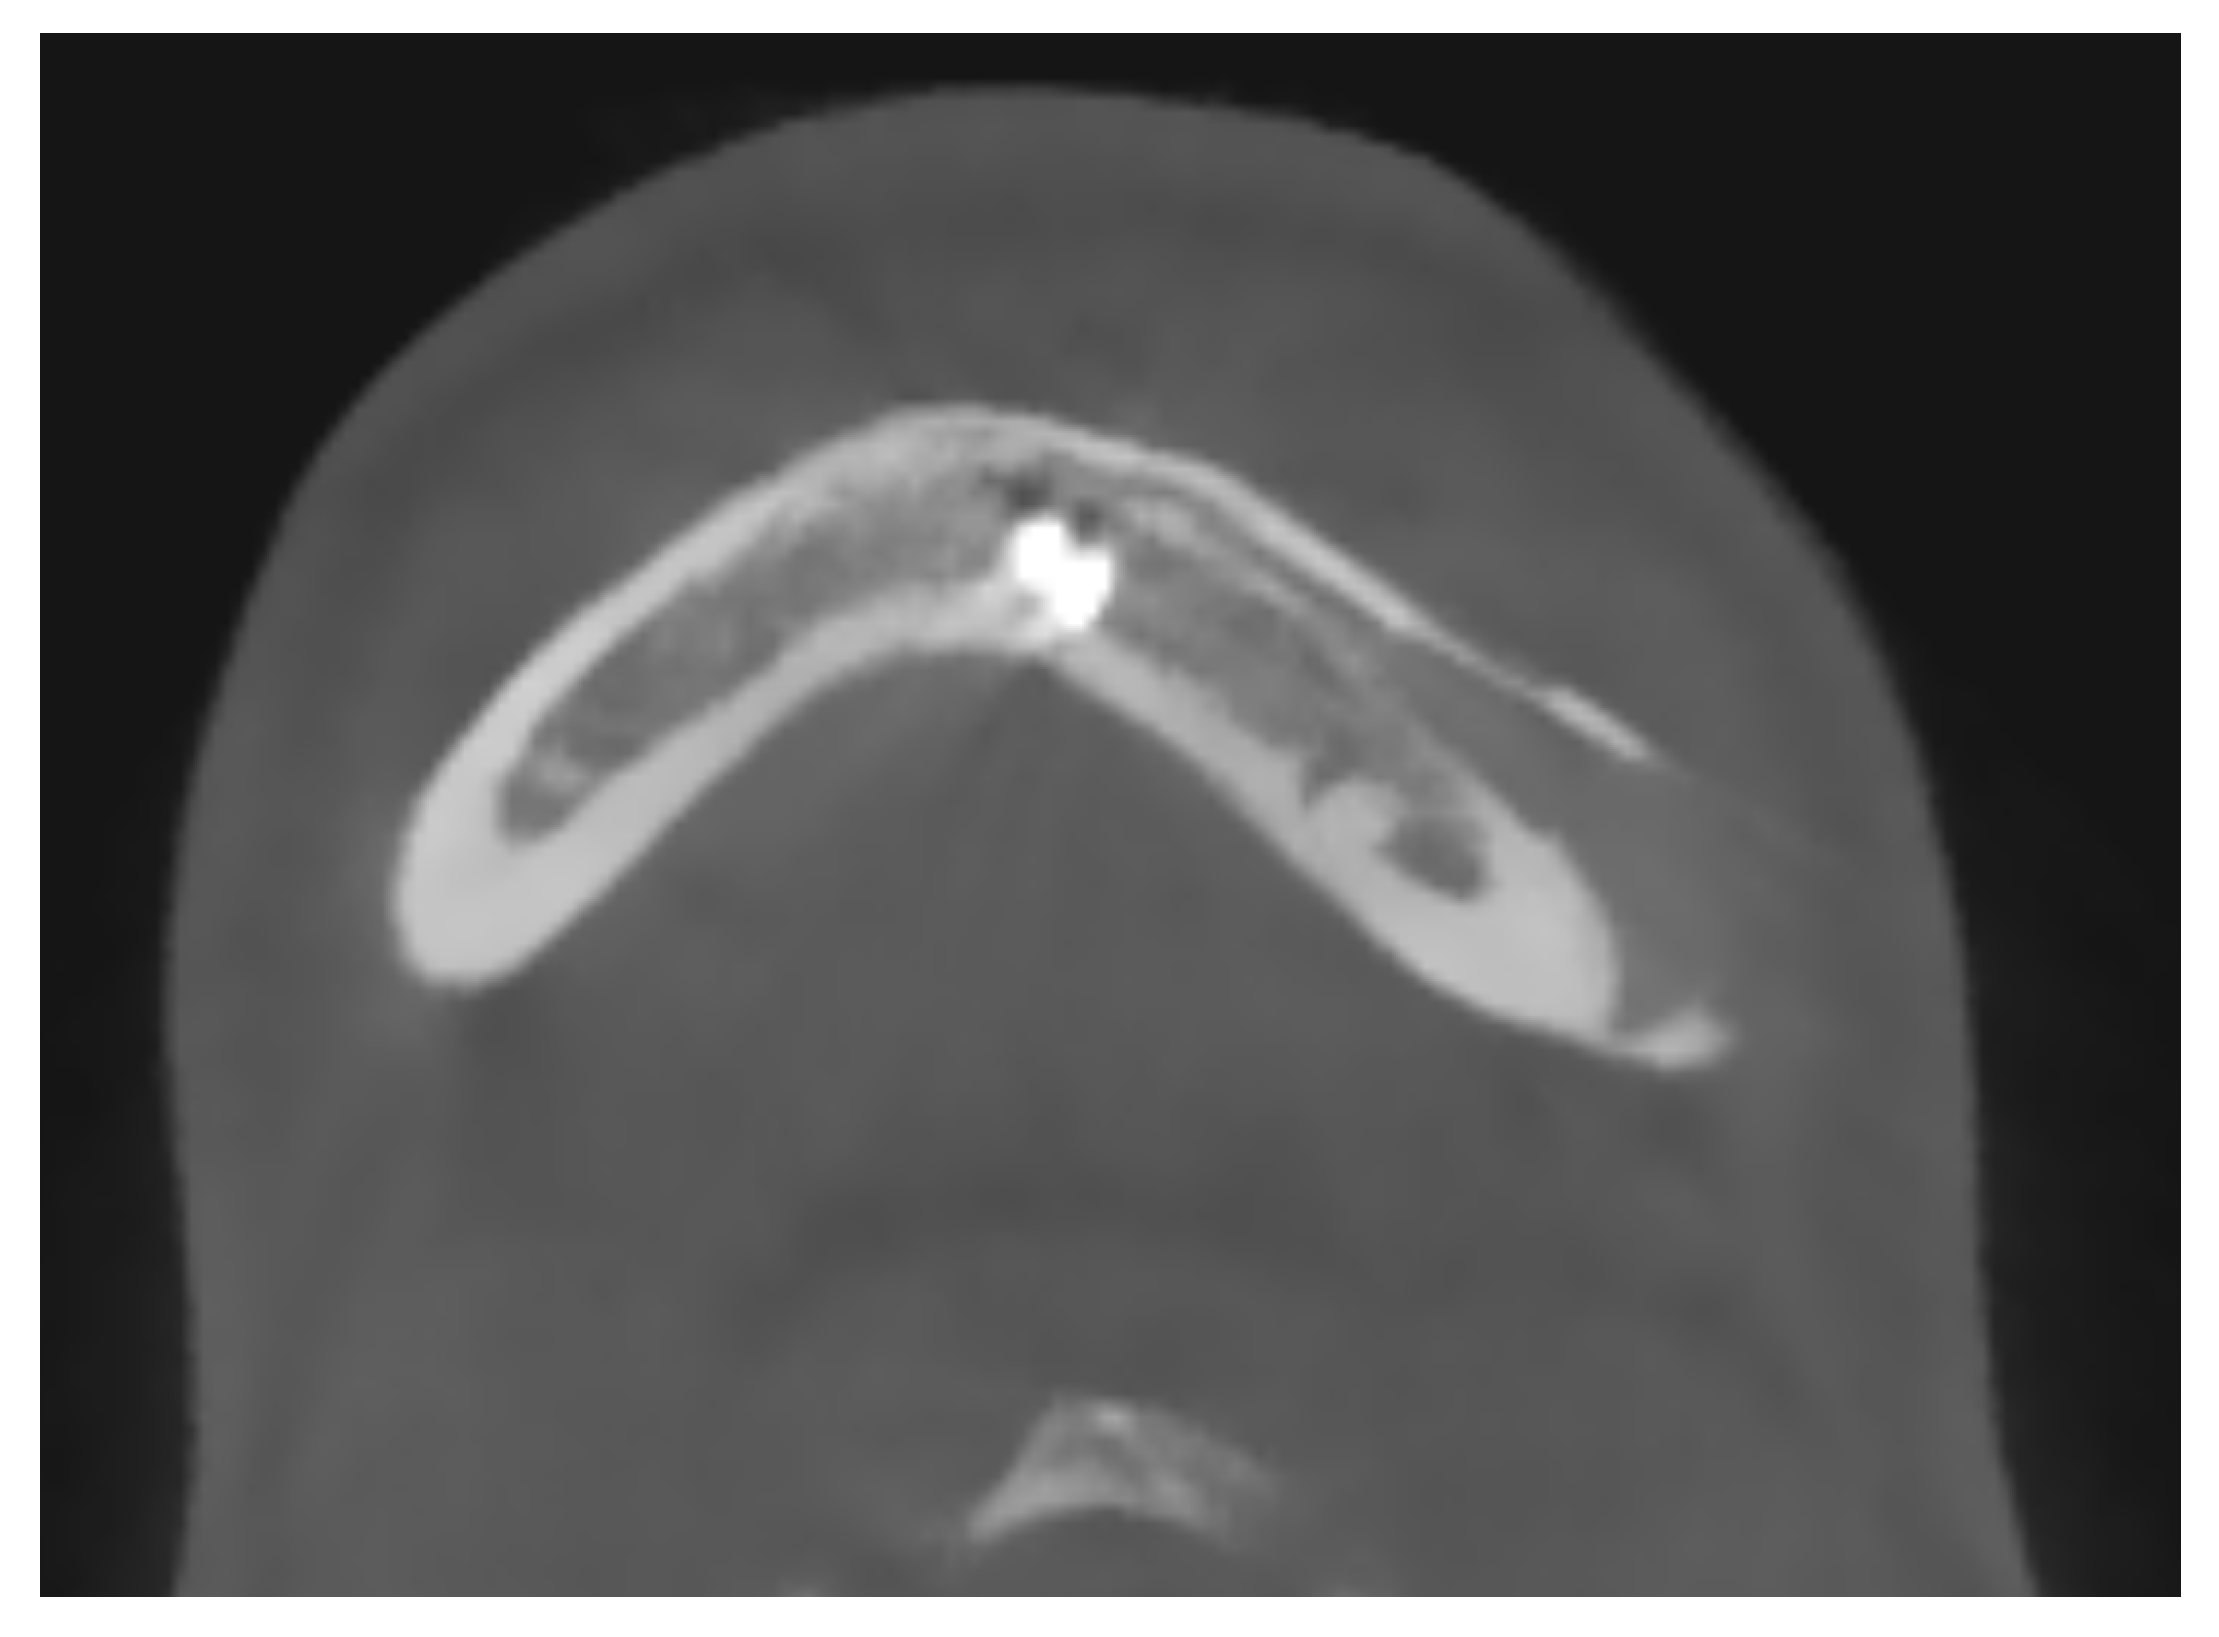

4.3. Importance of Intact and Fully Represented Periosteum

The integrity and representation of the periosteum are crucial factors in facilitating osseointegration and preventing complications associated with prosthetic implants. Indeed, regarding the periosteum reaction, what emerges from the HRCT is a non-radiologically appreciable alteration of the bone-periosteum profile, and this is a valuable sign of inert reaction of the periosteum to this material. The periosteum plays a vital role in bone healing and regeneration processes by providing a source of osteoprogenitor cells and growth factors. Preservation of the periosteum during implant surgery leads to enhanced bone formation and implant stability [52] [see Figure 4]. Conversely, damage or inadequate representation of the periosteum can impede osseointegration and increase the risk of implant failure.

Figure 4.

A maxillo-facial surgery case: bone regeneration around the prosthesis at the level of the left mandibular angle.